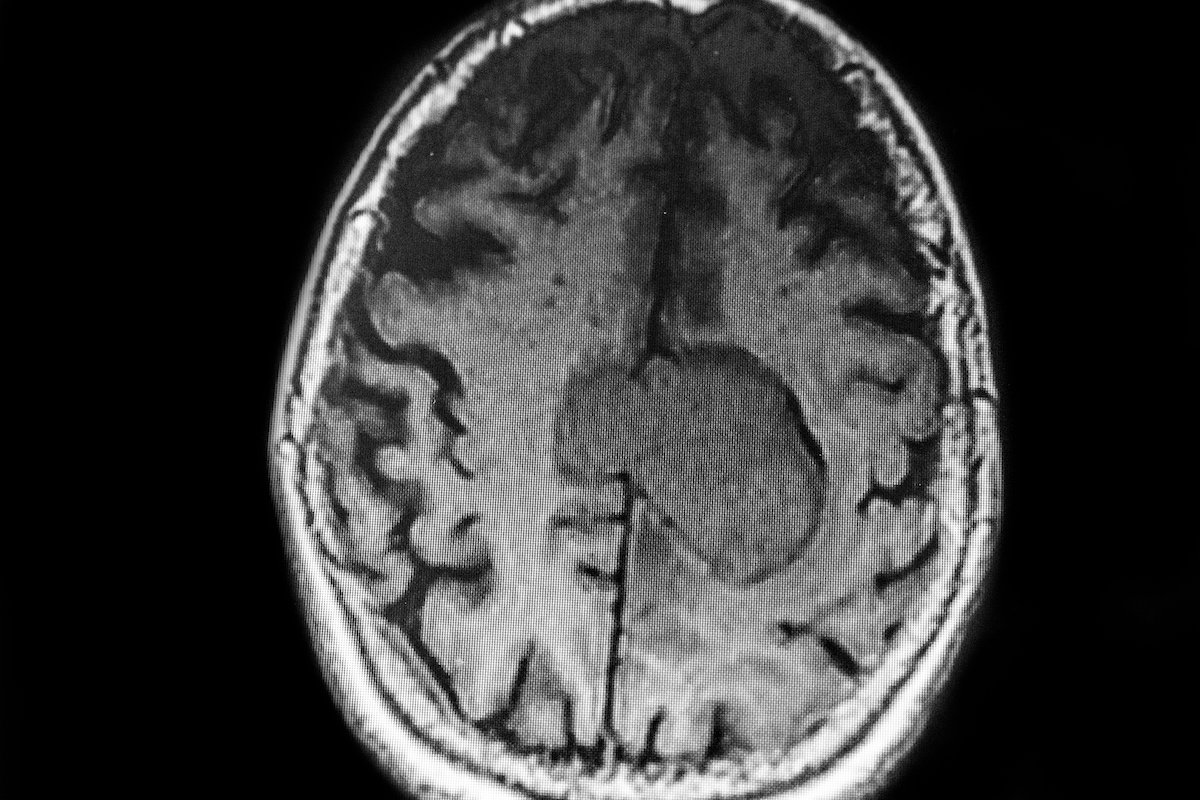

MRIs are a diagnostic tool for detecting brain tumors.

A meningioma is a type of tumor that originates in the meninges—the protective membranes that cover your brain and spinal cord within the central nervous system. It is the most frequently diagnosed type of tumor that forms in the head.

Meningioma is not technically a “brain tumor” because it does not grow from brain tissue. However, it can cause serious harm by pressing on the adjacent brain, nerves, and critical blood vessels.